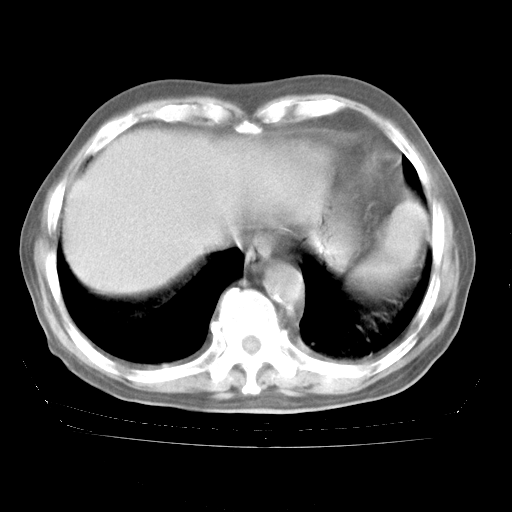

4月28日肺部CT——再次出现类似去年5月9日——透光度降低,“间质性”改变。

4月28日肺部CT——再次出现类似去年5月9日——磨玻璃样、间有“粟粒样”改变。

4月28日肺部CT